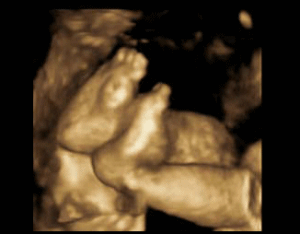

胎儿25周四维彩超照片

【胎儿25周四维彩超照片】和田新华康妇科医院专家专家介绍说:四维彩超是目前先进的彩色超声技术,四维彩超技术可以多方位、多角度的观察宝宝在腹中的动态以及宝宝自身发育情况。以下是25周胎儿四维彩超图片展现:

小脚丫在不停的动